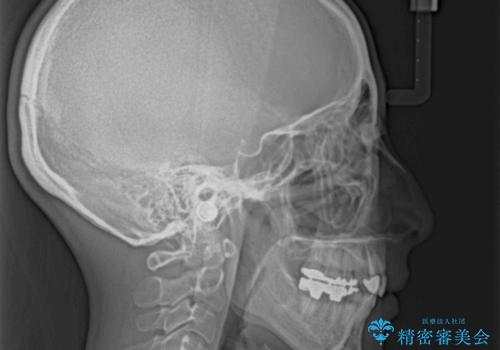

抜歯したスペースがなかなか閉じず、治療に時間はかかりましたが、術前術後のむし歯治療と合わせて3年10ヶ月で治療を終えることができました。

途中結婚により遠方に引っ越しをされたため、むし歯治療は取り急ぎ目立つところをセラミッククラウンとしましたが、今後落ち着いてきたら他の部分も行っていく予定です。